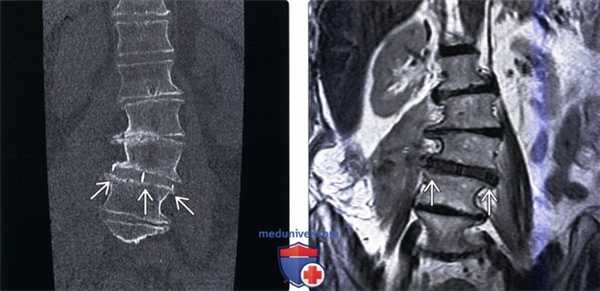

(Слева) КТ, фронтальный срез: дискогенный склероз замыкатель -ных пластинок L2-L3 слева и L3-L4 справа S3. Асимметричная дегенерация связана с перераспределением нагрузки у данного пациентов со сколиозом. Феномен вакуума виден в области нескольких межпозвонковых дисков.

(Справа) КТ, фронтальный срез: признаки тяжелого многоуровневого дегенеративного поражения межпозвонковых дисков с потерей высоты межтелового пространства, эбурнеацией кости и феноменом вакуума на уровнях L5-S1, L3-L4 и L2-L3. Обратите внимание на выраженный дискогенный склероз на уровне L5-S1 и левосторонний дегенеративный сколиоз.

(Слева) Т1-ВИ, фронтальная проекция: признаки умеренно выраженного левостороннего сколиоза с вершиной на уровне L3-L4. Имеет место правосторонний боковой листез L1 и L2 позвонков, потеря высоты межтеловых пространств и дегенеративные изменения замыкательных пластинок.

(Справа) Т2-ВИ, фронтальная проекия: признаки жировой инфильтрации костного мозга в смежных с дегенеративно измененными дисками участках. Обратите внимание на диффузные изменения замыкательных пластинок позвонков и боковой листез, связанный с тяжелой дегенерацией диска.

(Слева) КТ, фронтальный срез: случай левостороннего сколиоза грудопоясничного перехода и правосторонняя сколиотическая деформация поясничного отдела позвоночника. КТ с много -плоскостными реконструкциями изображения достаточно информативны в отношении оценки состояния позвоночника в целом и влияния листеза позвонков на состояние спинномозгового канала и нервных образований.